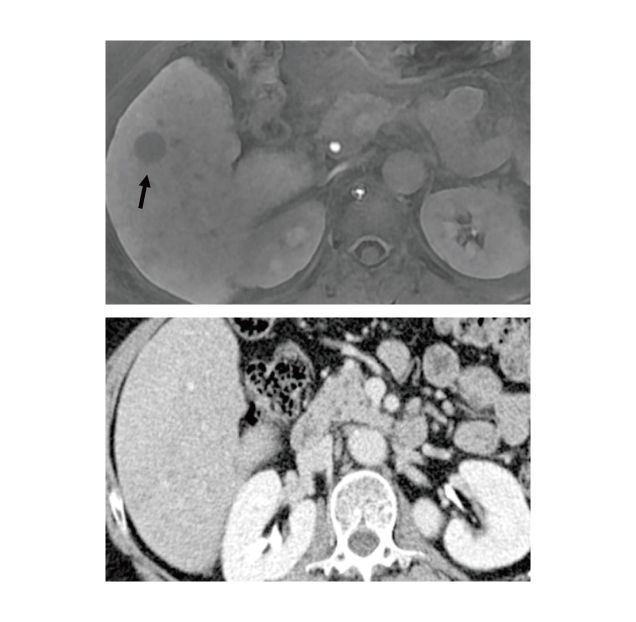

The major advantage of EOB-MRI is the improved detection of small lesions, ≤2 cm, compared with contrast-enhanced MRI or CT9,10. In a comparison between EOB-MRI and multiphasic CT (MDCT) in differentiating small HCC from arterial-enhancing pseudolesion (AEP) in cirrhotic liver, EOB-MRI yielded sensitivity higher than 90.9%, which was significantly higher than that yielded by MDCT (54.5%, p=0.001, Figure 2). Essentially, among the 44 HCC lesions examined, only 2 showed iso- or high signal intensity during HBP of EOB-MRI11. This indicates the high specificity of EOB-MRI in identifying small HCCs.

Figure 2. Images of hepatitis B liver cirrhosis, (A) EOB-MRI during HBP showing a 1.3 cm HCC (arrow) and (B) MDCT scan during delayed phase shows the lesion with iso-intensity to liver parenchyma11